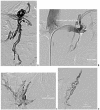

Nutcracker syndrome in adolescent with perineal pain: An interesting case of an adolescent with perineal pain due to pelvic congestion from nutcracker syndrome with relief after balloon venoplasty and sclerotherapy

Nutcracker phenomenon is the descriptor for a patient's anatomy whenever the left renal vein becomes compressed between the abdominal aorta and the superior mesenteric artery. Nutcracker syndrome is the terminology used when the nutcracker phenomenon is accompanied by symptoms including pain (abdominal, flank, pelvic), hematuria, and orthostatic proteinuria. Diagnosis can be made with Doppler ultrasound, venography, computed tomography, or magnetic resonance imaging. This case demonstrates some of the typical findings of nutcracker syndrome. The limited clinical features and interesting imaging findings, in addition to the young age of the patient, make this a notable case.